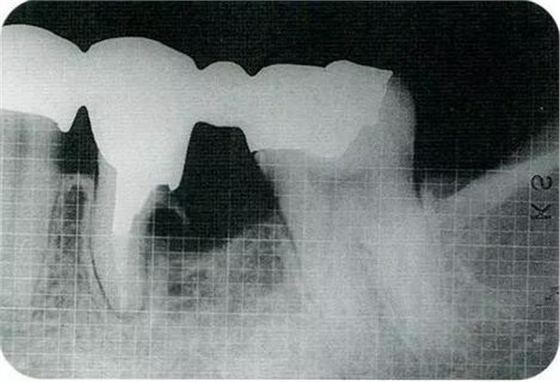

▼圖16-4

圖16-4進(jìn)行牙齒分割時(shí),如圖所示一樣,要確保分割去除的牙根邊緣不會(huì)殘留在牙槽中間骨脊。如果有邊緣殘留,會(huì)造成軟組織發(fā)紅,引發(fā)炎癥。

▼圖17

圖17將右上6近中頰側(cè)根拔除,考慮到修復(fù)物清潔性的情況下進(jìn)行備牙。牙齒分割后如果有邊緣殘留,就會(huì)使切割面的牙齦發(fā)紅無(wú)法治愈。